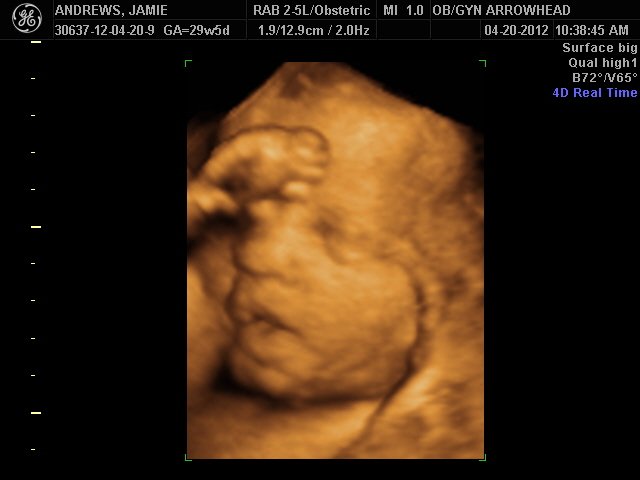

We offer complimentary 3D/4D Ultrasounds to all our OB patients around 30 weeks! The following photos are some examples of our work, shown with permission from our patients.